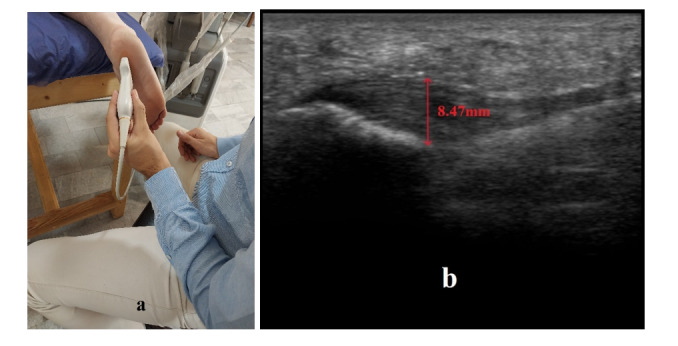

Methods: This was an add-on design a single-blind randomized clinical trial that was conducted with 30 chronic plantar fasciitis patients. Subjects were randomized into two groups: the Gastrocnemius Myofascial Release (G-MFR) group and the Chain Myofascial Release (C-MFR) group. Each participant underwent four MFR sessions over two weeks. Outcome measures included the Numeric Pain Rating Scale (NPRS), the Foot Function Index (FFI), and ultrasound-based evaluations of plantar fascia thickness. Due to the non-normal distribution of change scores, between-group comparisons were performed using the Mann-Whitney test with the Hodges-Lehmann estimator, and effect sizes were reported using r values.

Results: Both groups exhibited significant improvements in NPRS and FFI scores post-intervention (P<0.001), with the C-MFR group showing greater reductions in both measures (for NPRS: P=0.004, r=0.686 and for FFI: P=0.004, r=0.518). However, while plantar fascia thickness decreased significantly in the C-MFR group (P=0.001, r=0.829), no significant change was observed in the G-MFR group (P=0.422, r=0.206). The reduction in thickness for C-MFR compared to G-MFR was not statistically significant (P=0.233, r=0.222).